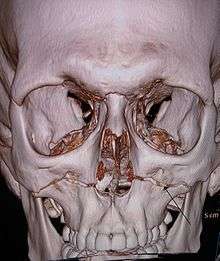

Diagnosis

Diagnosis is suspected by physical exam and history, in which, classically, the hard and soft palate of the midface are mobile with respect to the remainder of facial structures. This finding can be inconsistent due to the midfacial bleeding and swelling that typically accompany such injuries, and so confirmation is usually needed by radiograph or CT.[3]